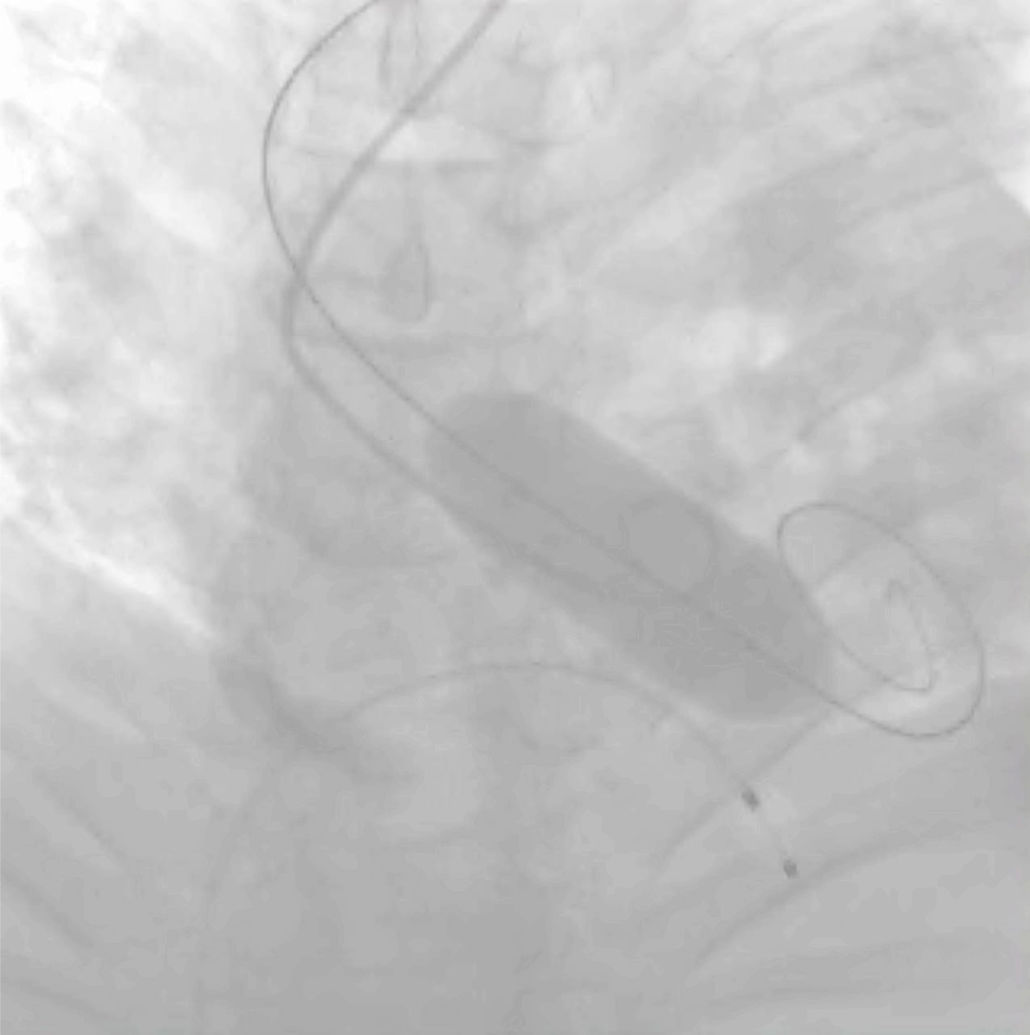

Pre-dilataciónEl efecto mecánico del balón (fractura del calcio y separación de las cúspides fusionadas) incrementa el área del orificio valvular y permite una progresión menos traumática del dispositivo TAVI (fig. 1). Además, acondiciona la válvula para el implante, asegura una expansión uniforme de la prótesis y reduce la fuerza radial. Con ello se consigue reducir la incidencia de malposición y regurgitación perivalvular (RPV). El diseño de las válvulas autoexpandibles les confiere una menor fuerza radial, motivo por el que pueden quedar infraexpandidas al desplegarse sin valvuloplastia previa, máxime en válvulas severamente calcificadas6.

La pre-dilatación es también una herramienta complementaria a la tomografía computarizada (TAC) que aporta valiosa información cuando existen dudas en la selección de la talla protésica, en pacientes con anatomía hostil (aorta angosta) o ante elevado riesgo de oclusión coronaria (nacimiento ostial bajo). Su despliegue permite evaluar la interacción del velo con la pared aórtica y así adelantar una posible obstrucción durante el implante valvular.